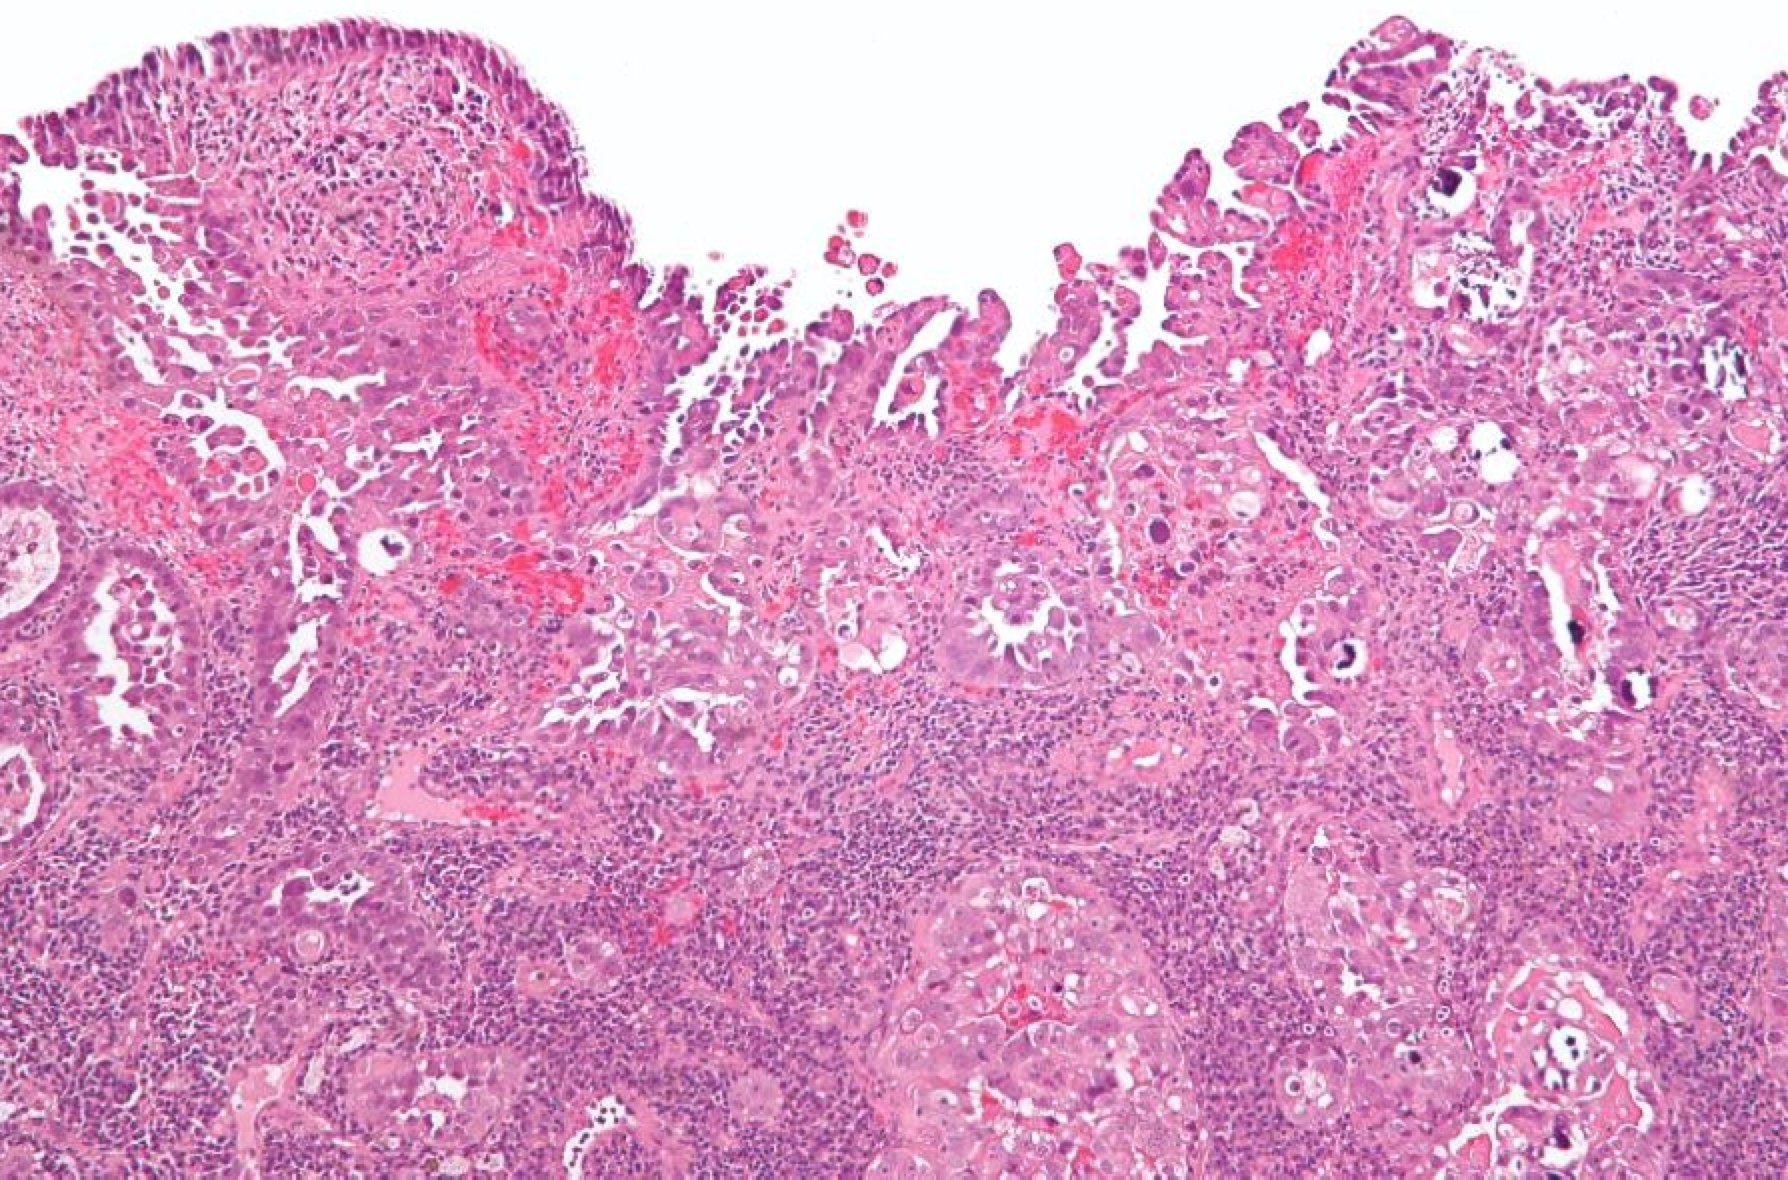

The majority of cases are endometrioid, which is divided into low, intermediate and high grades (Grade I-III). These are commonly low grade, estrogen responsive, and are much more common. Papillary serous and clear cell cancers are much more agressive and should be considered high risk disease.

More recently, histopathlogists have divided the two groups into "Type I" and "Type II" cancers. Type II are the serous and clear cell cancers, which are generally more agressive and much less common than endometriod cancers.

Endometrioid: Big well structured glandsPapillary serous with sheets of cells between disorganized glands